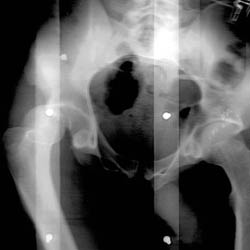

Skeletal Trauma > Pelvis & Hips > Pelvis and Hips Quiz

Pelvis and Hips Quiz

True or False 1. Posterior hip dislocations are less common than anterior. 2. Malgaigne fractures are unstable. | ||||||